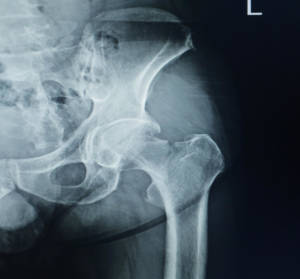

I distretti corporei maggiormente coinvolti sono: anche, colonna vertebrale, polsi, spalle e femore. Da notare che una frattura al femore, può condurre il soggetto colpito a una condizione di disabilità fisica.

Le sue conseguenze sono una diminuzione della densità minerale ossea e un aumento della fragilità e debolezza dell’apparato scheletrico con predisposizione alla comparsa di fratture al collo del femore, al femore, ai corpi vertebrali, all’avambraccio e alla parte prossimale vicino alla spalla per quanto concerne la frattura dell’omero.

Spesso chi ha avuto fratture al femore presenta fratture vertebrali senza saperlo. I Pazienti che hanno subito una frattura al collo del femore, presentano in oltre il 50% dei casi, anche delle fratture vertebrali.

Una frattura al femore può anche ridurre il soggetto colpito in condizioni di disabilità fisica nel 20% – 30% dei casi.